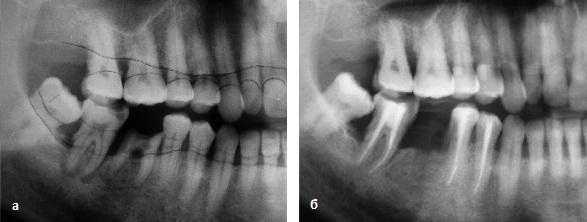

Оценку эффективности лечения ЭПП мы проводили на основании клинических и рентгенологических критериев (рис. 3): наличие жалоб на боли при накусывании, подвижность, гноетечение из кармана или фистулы; на основании рентгенограмм оценивали состояние костной ткани пародонта и периапикальной области.

Рис. 3. а - ЭПП в области зуба 47; б - восстановление костной ткани в периапикальной области зуба 47 и стабилизация уровня костной ткани альвеолярного отростка после проведенного лечения.

В течение первых 3 мес из-за отсутствия положительной динамики после эндодонтического лечения было удалено 12,5% от всех пролеченных зубов. При оценке рентгенологической картины на прицельных рентгенограммах положительная динамика в виде практически полного восстановления костной ткани в периапикальной области отмечена в 35% случаев, а в виде уменьшения периапикального очага - в 50%. У зубов верхней челюсти и зубов с поражением фуркации положительной динамики не выявлено.

Комплексное эндодонто-пародонтологическое лечение позволяет добиться восстановления костной ткани в периапикальной области и прекращения ее воспалительной резорбции, а назначение НПВП Кеторол в период после лечения способствует купированию БС.